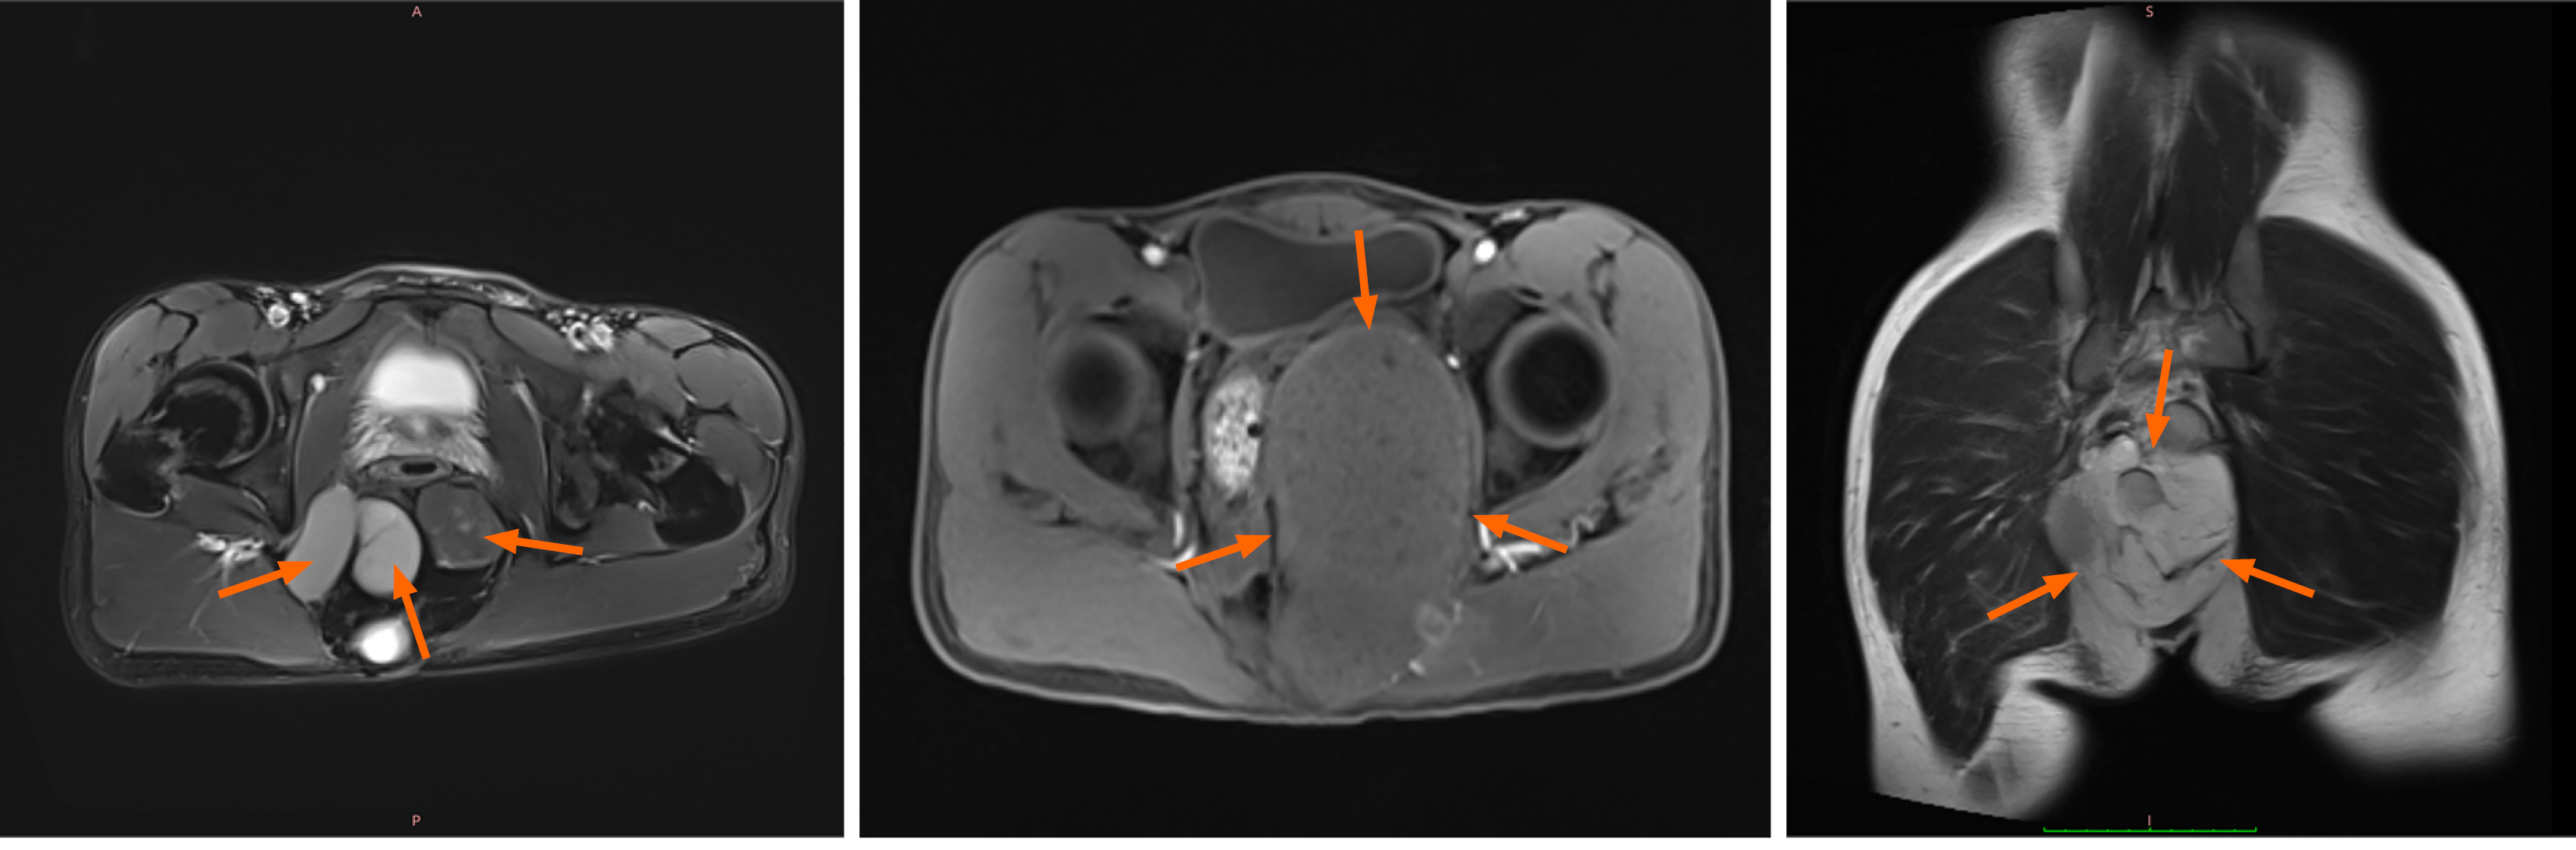

Figure 2 Magnetic resonance imaging images of the tumor in some patients.

The location of the tumor is indicated by the orange arrow.